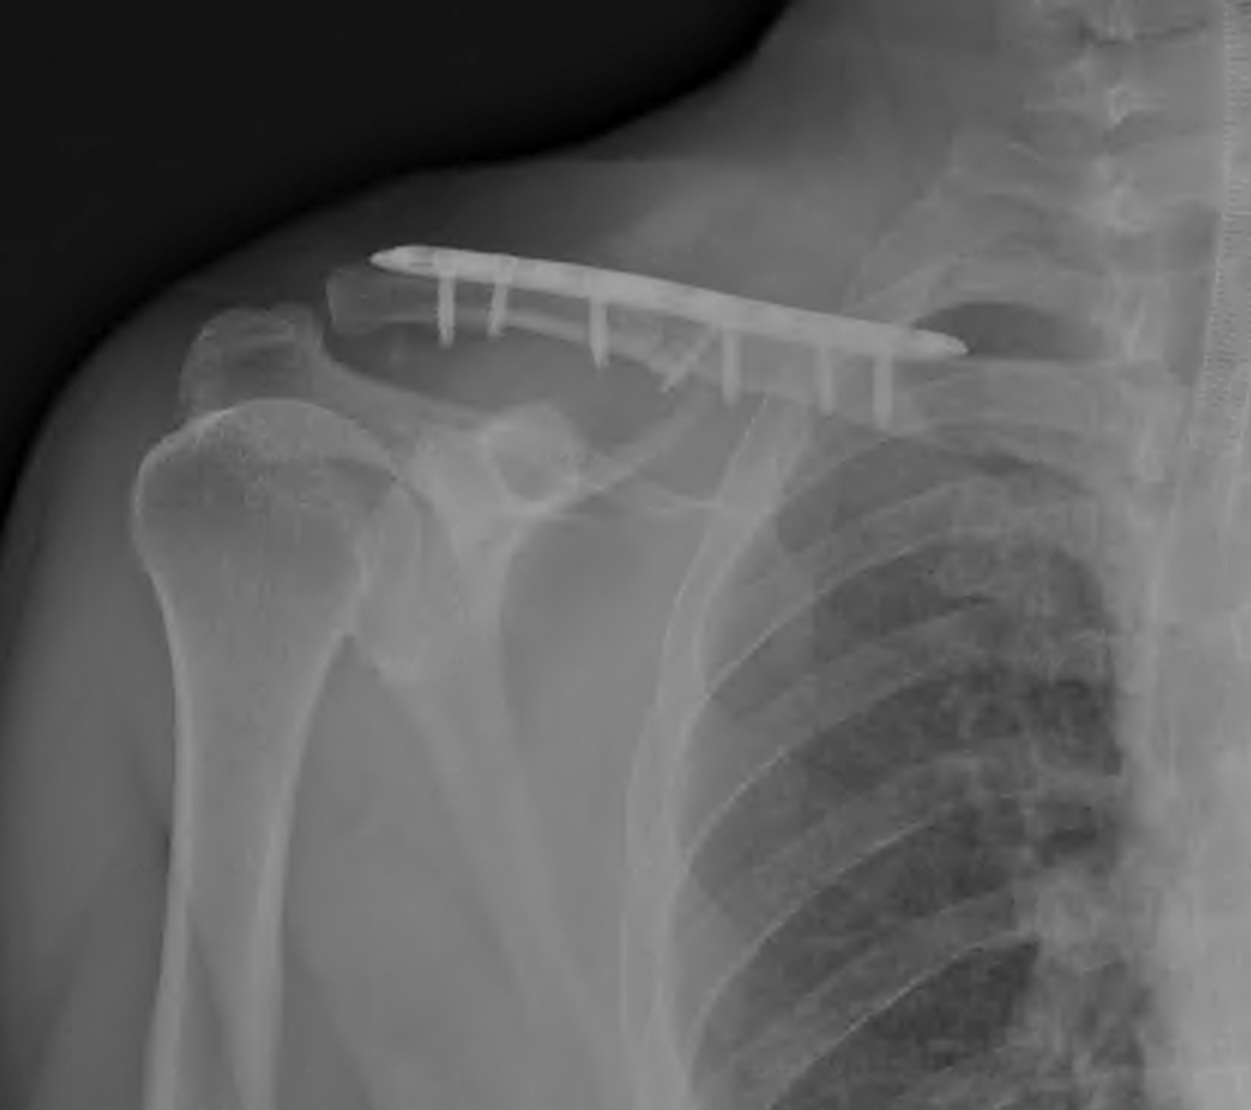

Klavikula kırık ameliyatı

Köprücük kemiği (klavikula) kırık ameliyatı